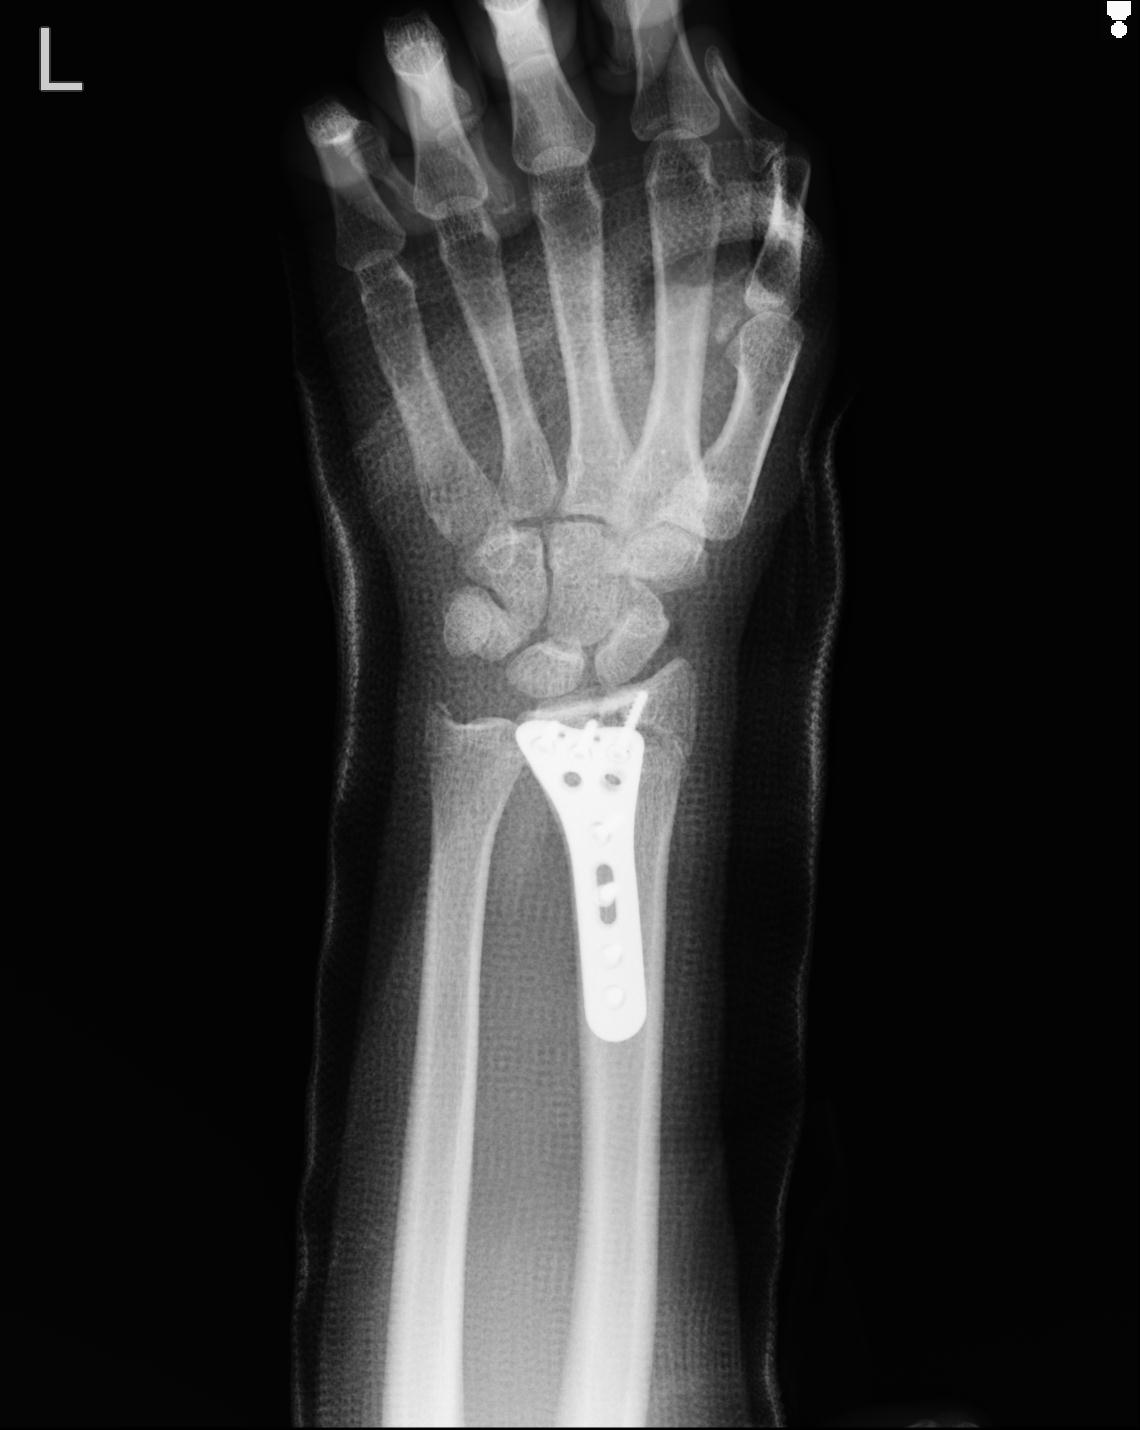

102766 1/5 1/12 左手関節 4R 28歳男性 左橈骨遠位端

102739 12/30 1/5 左手関節 4R 92歳女性 橈骨遠位端